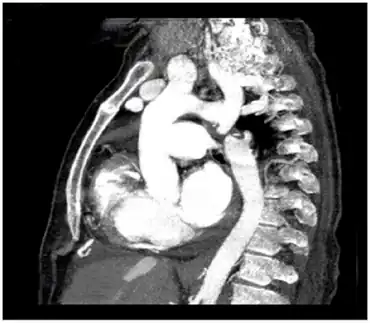

| CT angiography showing type A interrupted aortic arch | |

- Type A: The aortic arch is interrupted after the left subclavian artery.[3][6]